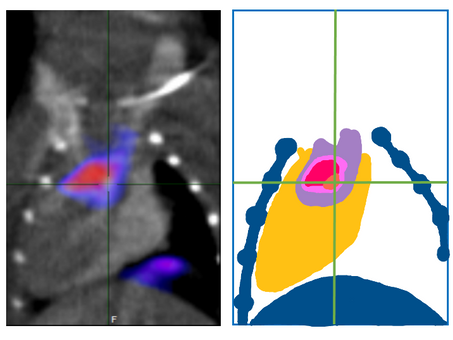

Studying mice to help prevent heart attacks and stroke

Research from Erasmus Medical Center Rotterdam, in the Netherlands, has used animal imaging studies to identify when arteries become...